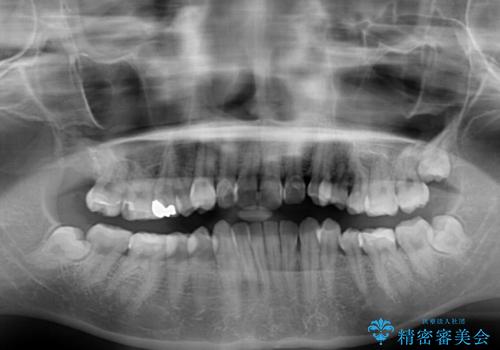

- 上下歯列全体のデコボコを気にして来院された患者様です。

主に下顎歯列全体の後方移動とIPR(歯と歯の間を削る)によってデコボコが解消するように設計し、インビザラインにより治療を行うこととしました。

奥歯の知覚過敏が顕著となり、その影響で奥歯の咬み合わせ改善のための顎間ゴムの装着ができず、咬合を仕上げるまでに長い期間を要することとなりました。